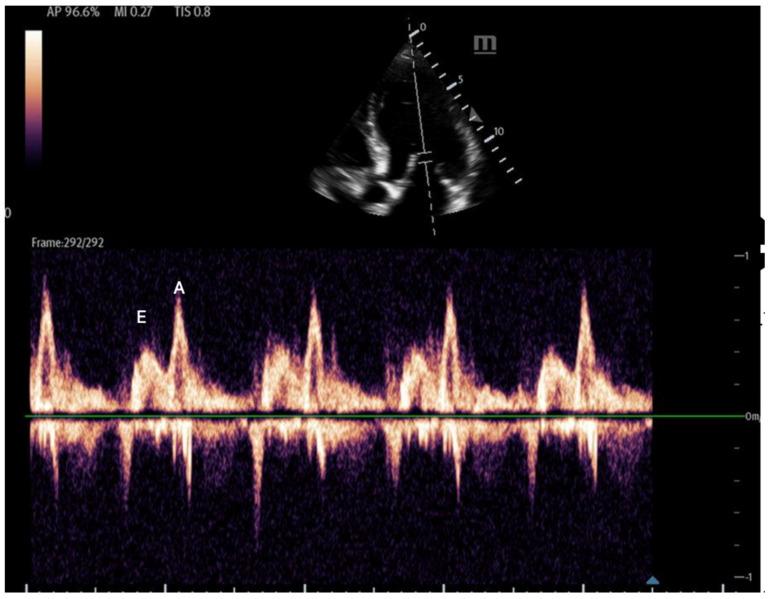

床旁超声在血流动力学评估中的应用

Point-of-Care Ultrasound Use in Hemodynamic Assessment.

Hemodynamic assessment is critical in emergency and critical care for preventing, diagnosing, and managing shock states that significantly affect patient outcomes. Point-of-care ultrasound (POCUS) has become an invaluable, non-invasive, real-time, and reproducible tool for bedside decision-making. Advancements such as Doppler imaging, advanced critical care ultrasonography, and transesophageal echocardiography (TEE) have expanded its utility, enabling rapid and repeatable evaluations, especially in complex mixed shock presentations. This review explores the role of POCUS in hemodynamic monitoring, emphasizing its ability to assess cardiac output, filling pressures, and vascular congestion, facilitating shock classification and guiding fluid management. We highlight an extensive array of POCUS techniques for evaluating right and left cardiac function and review existing literature on their advantages, limitations, and appropriate clinical applications. Beyond assessing volume status, this review discusses the role of POCUS in predicting fluid responsiveness and supporting more individualized, precise management strategies. Ultimately, while POCUS is a powerful tool for rapid, comprehensive hemodynamic assessment in acute settings, its limitations must be acknowledged and thoughtfully integrated into clinical decision-making.

血流动力学评估在急诊和重症监护中对于预防、诊断和处理显著影响患者预后的休克状态至关重要。床旁即时超声检查(POCUS)已成为一种用于床边决策的宝贵、非侵入性、实时且可重复的工具。诸如多普勒成像、高级重症监护超声检查和经食管超声心动图(TEE)等技术进步扩展了其用途,能够进行快速且可重复的评估,尤其是在复杂的混合性休克表现中。本综述探讨了POCUS在血流动力学监测中的作用,强调其评估心输出量、充盈压和血管充血情况的能力,有助于休克分类并指导液体管理。我们重点介绍了一系列用于评估左右心功能的POCUS技术,并回顾了关于它们的优势、局限性及适当临床应用的现有文献。除了评估容量状态外,本综述还讨论了POCUS在预测液体反应性以及支持更个体化、精确的管理策略方面的作用。最终,虽然POCUS是急性情况下进行快速、全面血流动力学评估的有力工具,但必须认识到其局限性并谨慎地将其纳入临床决策。